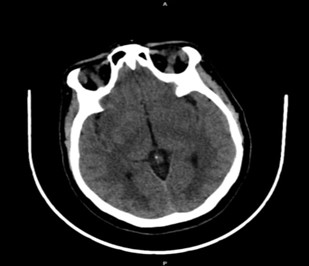

The patient was transferred to the Surgical Intensive Care Unit (SICU) for further management. A CT brain scan (Fig. 1) was performed, which revealed:

- Bilateral hypodense areas in the subcortical white matter of the parietal and occipital lobes, more prominent in the occipital region

- Diffuse sulcal effacement with preserved gray-white matter differentiation

- No evidence of intracranial hemorrhage, territorial infarction, mass effect, or midline shift

- Well-aerated paranasal sinuses and mastoid air cells

Figure 1: CT image showing bilateral subcortical hypodensities.

PRES is typically associated with acute, severe hypertension and is most commonly observed in women with preeclampsia and eclampsia, as well as in those with other conditions associated with elevated blood pressure, such as renal disease and immunosuppressive therapy. The condition is thought to result from a breakdown of the blood-brain barrier (BBB), leading to vasogenic edema, particularly in the posterior regions of the brain. The occipital lobes are most commonly affected, which explains the characteristic visual disturbances that occur in a significant proportion of patients with PRES (Marra et al., 2014). In this case, the patient developed visual loss, which was likely due to edema affecting the occipital cortex. The CT scan findings of bilateral hypodense areas in the subcortical white matter and the mild brain edema are consistent with the pathophysiology of PRES.

Neuroimaging, particularly MRI and CT scans, plays a crucial role in diagnosing PRES and differentiating it from other neurological conditions that can arise in the setting of severe hypertension, such as intracranial hemorrhage or stroke. In this case, the CT brain scan revealed bilateral hypodense areas in the subcortical white matter of the occipital and parietal lobes, a finding that is highly suggestive of PRES. While CT can identify structural changes associated with PRES, MRI is generally considered more sensitive and can provide more detailed information regarding the extent and location of the edema. The absence of intracranial hemorrhage, territorial infarction, and space-occupying lesions in the imaging further supported the diagnosis of PRES and helped exclude other potential causes of the patient’s neurological symptoms.